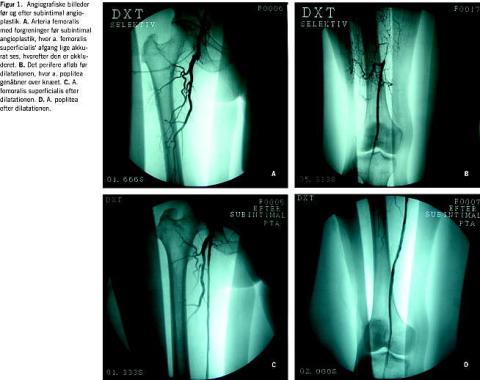

Rekanaliseringen blev foretaget som beskrevet af Bolia et al [6], og alle blev foretaget af den samme speciallæge i radiologi. Under lokalbedøvelse blev a. femoralis punkteret anterogradt på den ipsilaterale side eller retrogradt på den kontra-laterale side. Et fem french specialkateter med bøjet spids (vertebraliskateter, Cook) blev ført til okklusionens proksimale del og derefter subintimalt. En hydrofil 0,035'' guidewire blev brugt til at positionere kateteret videre ind subintimalt, og den subintimale position blev verificeret med kontrast. Herefter blev guidewire og kateter skubbet forbi okklusionen subintimalt og videre ind i det sande, åbne lumen distalt for okklusionen. Den subintimale kanal blev dilateret i ca. 30 s konsekutivt med en 3-6 mm ballon, afhængigt af det originale kars diameter. Eventuelle stenoser af den subintimale neokanal blev dilateret lokalt. To patienter fik indlagt en stent proksimalt i neokanalen for at holde den proksimale del åben. Under indgrebet blev der givet 5.000 enheder heparin intravenøst, og tre timer efter indgrebet blev der givet 7.000 enheder tinzaparin subkutant. Teknisk succes blev defineret som angiografisk påvist åben subintimal neokanal uden væsentlige stenoser. Figur 1 viser angiografiske billeder før og efter subintimal angioplastik.